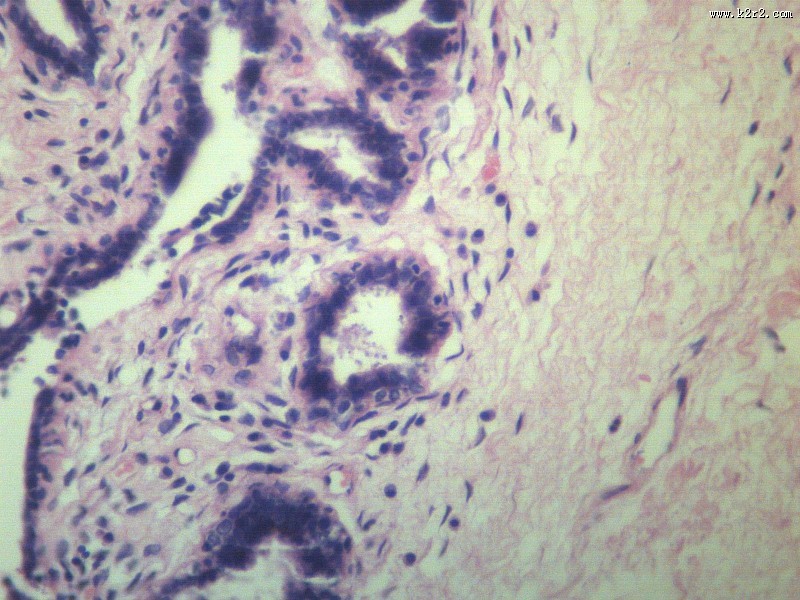

fibroadenoma of breast

乳腺纤维腺瘤

肿瘤显微切片